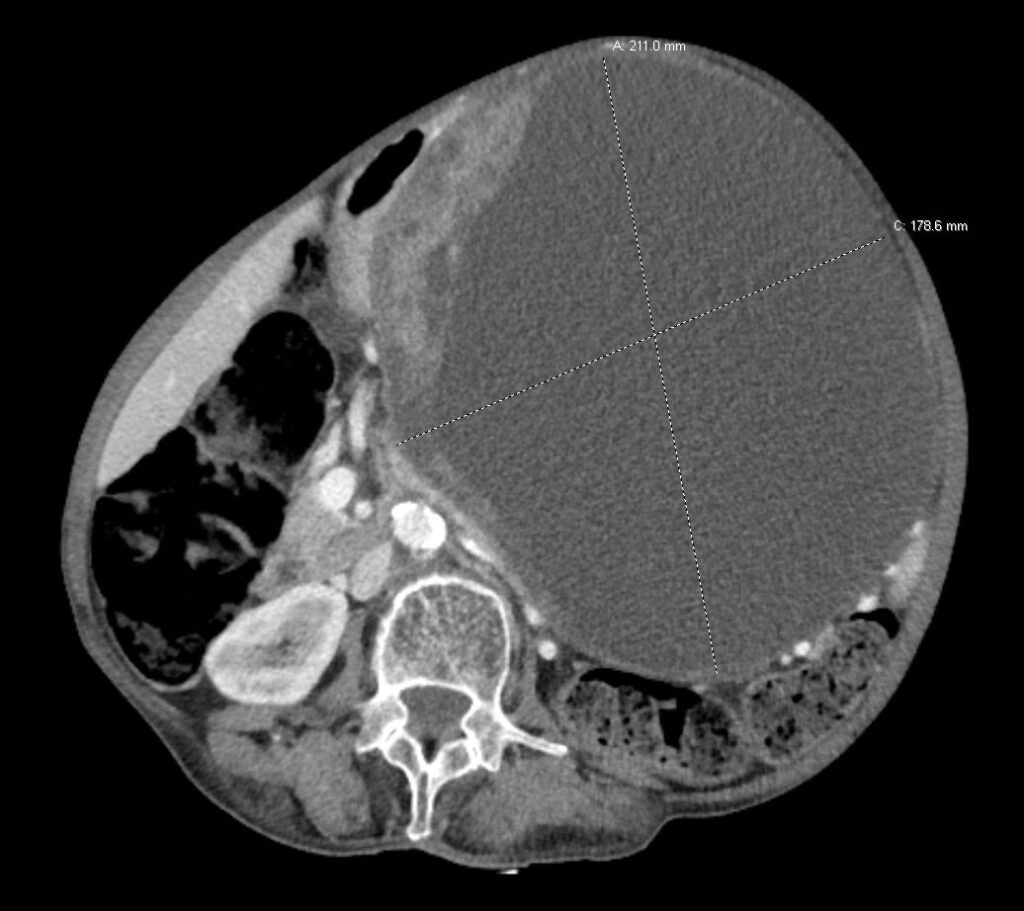

وأظهرت الفحوصات والتقييمات الطبية الشاملة إصابة المستفيدة بورم سرطاني في المستقيم، إضافة إلى وجود ورم كيسي كبير في المعدة بلغ حجمه 21 × 18 سم، ما استدعى إعداد خطة علاجية دقيقة ومتكاملة وفق أفضل البروتوكولات الطبية المعتمدة.

وشملت الخطة العلاجية تقديم العلاجين الكيميائي والإشعاعي قبل التدخل الجراحي، بهدف تحسين النتائج العلاجية ورفع كفاءة الإجراء الجراحي. وبعد استكمال المراحل العلاجية، أُجريت للمريضة عملية جراحية ناجحة تضمنت استكشاف واستئصال الورمين في المعدة والمستقيم.